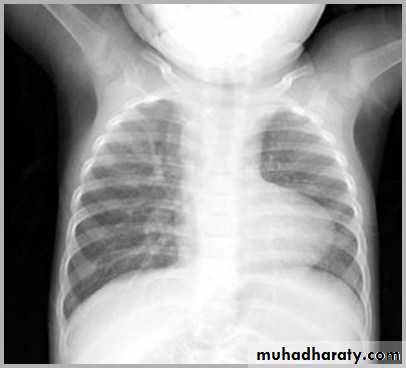

CXR of a neonate ,PA view shows thymus gland (normal finding not a disease ) with indentationsUL: Thymus Indentation sign. UR: Thymic wave sign, Lower: Thymic Sail sign

normal chest XR of the infant( normal thymus gland) Sail sign